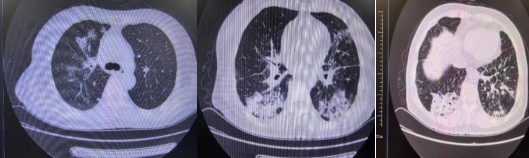

1個月后復查胸部CT

明確病因后,戚剛強主任團隊開展有針對性的治療,時刻關注患者病情變化。在醫護人員的悉心照護下,患者病情逐漸穩定,癥狀消失,復查胸部CT顯示較前明顯吸收,治療有效。